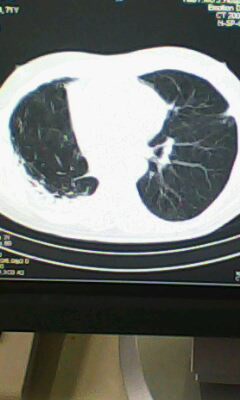

标题: CT25675:男 71 肺癌部分切除术后 3年 [打印本页]

标题: CT25675:男 71 肺癌部分切除术后 3年

右肺癌切除术后。

右侧胸膜肥厚。

1.右肺符合肿瘤切除术后ct表现。

2.左肺炎症。

术后改变,双肺内纤维索条影考虑与放疗有关。